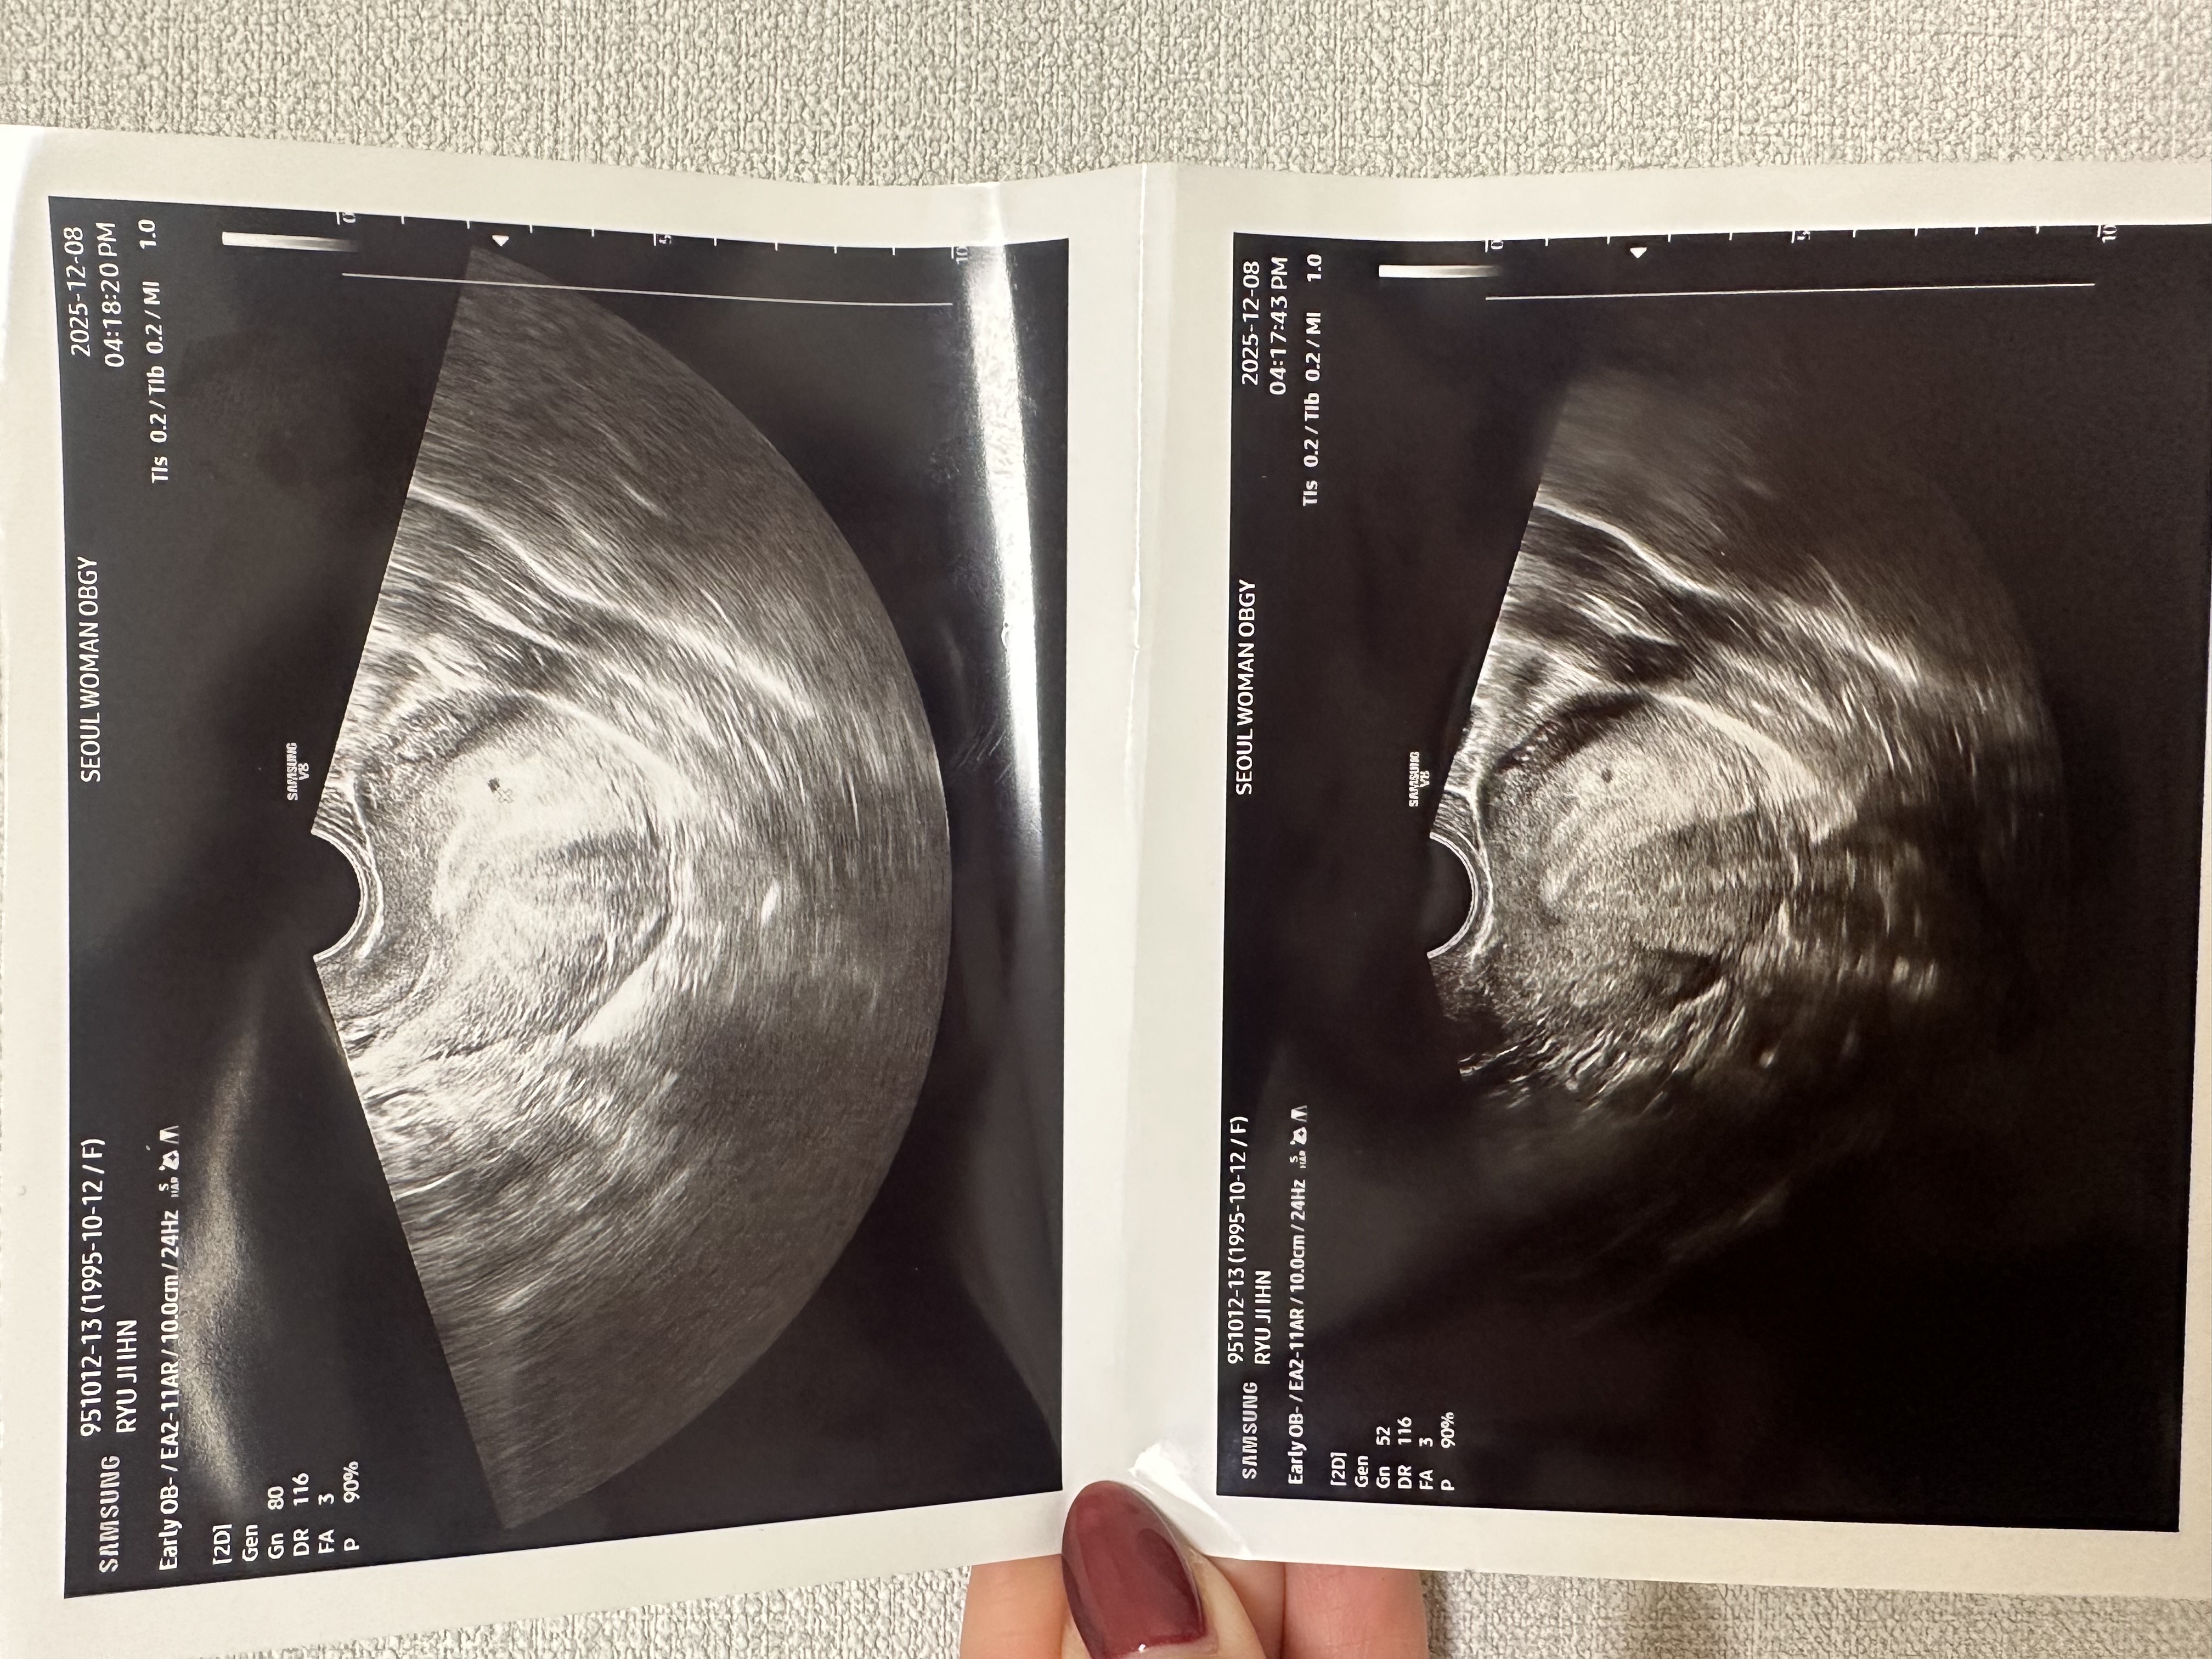

네이버주수 4주5일차/배란20일차 2025.12.1 월요일 배란일13일차 피검사 수치129.3 2025.12.5 금요일 배란17일차 피검사 수치 865.7 2025.12.8 월요일 배란20일차 피검사 수치 2050 이렇게 오늘까지 더블링 됬는데 조그만 점이 아기집일수도 있고 아닐수도 있다는데 일단 아기집 추정으로 소리듣고 이번주 목요일에 다시 가서 아기집 봐야된다고 하셔서 다시병원 갑니다 혹시나 아기집이 아닐까ㅠ 안커지면어떡하지 라는 생각에 초음파를 봐도 불안하네요ㅠㅠ 다들어떠셨나요??